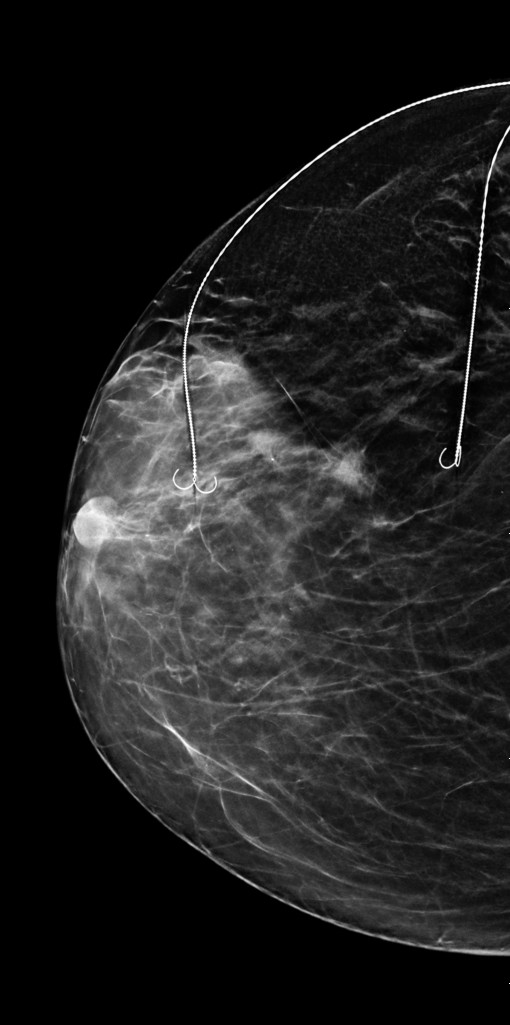

Este vorba despre o procedură modernă, denumită Bracketing cu două harpoane, o tehnică ce permite localizarea precisă a leziunilor canceroase multiple și excizia acestora cu păstrarea țesutului sănătos cât mai intact. O intervenție de finețe, posibilă doar prin colaborarea unei echipe multidisciplinare și folosirea unor metode avansate de ghidaj imagistic.